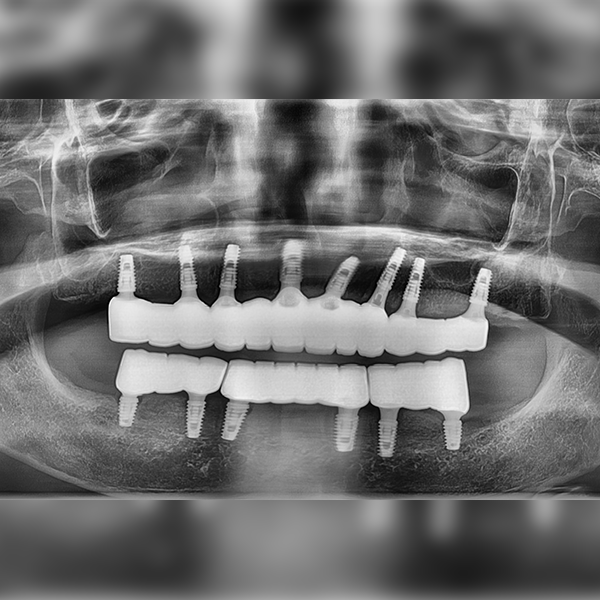

Oneday Шүдний эмнэлэг

Бүтэн эрүү / Яс шилжүүлэн суулгах | Унтуулгатай

Тохиолдол.53 70-аад насны Им*жа 2021-03-30 / 2021-04-02